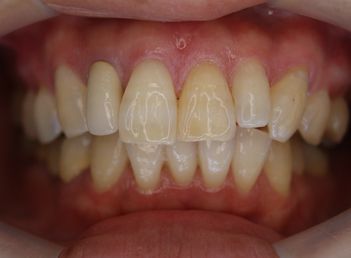

フィステル(瘻孔)があって、変色している症例。根管治療をすると、フィステルは消失。

DSC00513.JPG

DSC00520.JPG

レントゲン写真がこちら。根管治療&根管充填(この場合キャナルス&ガッターパーチャ)後。

で、漂泊してCR充填すればきれいに出来上がり。